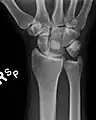

![]() Left hand anterior view (palmar view). Lunate bone shown in red. | |

The lunate bone (semilunar bone) is a carpal bone in the human hand. It is distinguished by its deep concavity and crescentic outline. It is situated in the center of the proximal row carpal bones, which lie between the ulna and radius and the hand. The lunate carpal bone is situated between the lateral scaphoid bone and medial triquetral bone.

The lunate is a crescent-shaped carpal bone found within the hand. The lunate is found within the proximal row of carpal bones. Proximally, it abuts the radius. Laterally, it articulates with the scaphoid bone, medially with the triquetral bone, and distally with the capitate bone. The lunate also articulates on its distal and medial surface with the hamate bone.[2]: 708 [3]